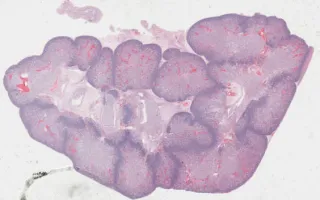

Kidney, Simpson-Golabi-Behmel Syndrome

Simpson-Golabi-Behmel Syndrome

In this syndrome, Wilms’ tumour (nephroblastoma) is common. However, in this case, the finding is nephroblastomatosis, a proliferation of the blastemal component which is considered a precursor to Wilm’s tumour.

This slide shows H&E stain of kidney. See Related Content section for other stains, ovotestis slides, and specimen photograph: